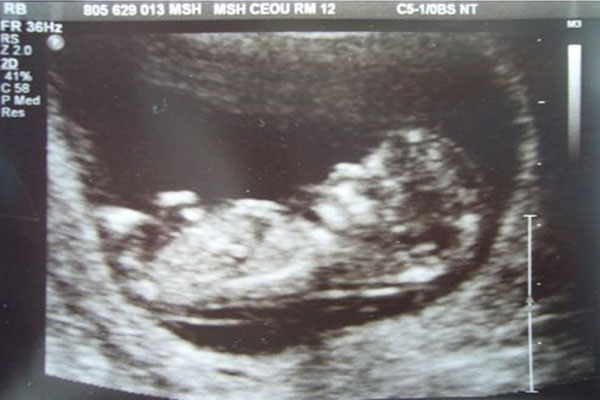

有没有怀孕,也可以直接去医院做血检hcg检查,通过身体里血液hcg值的变化,可以判断出有没有怀孕,这种方法是比较准确靠谱的,而且也是非常科学的好方法。